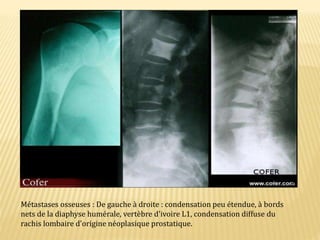

Métastases osseuses : De gauche à droite : condensation peu étendue, à bords

nets de la diaphyse humérale, vertèbre d'ivoire L1, condensation diffuse du

rachis lombaire d'origine néoplasique prostatique.

Métastases osseuses :De gauche à droite : condensation peu étendue, à bords nets de la diaphyse humérale, vertèbre d'ivoire L1, condensation diffuse du rachis lombaire d'origine néoplasique prostatique.